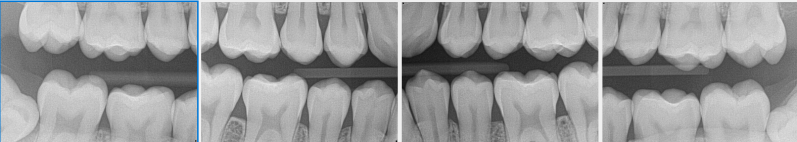

Set of bitewings (with direct sensor)

Set of bitewings made with NOMAD X-ray unit

Set of bitewings made on 12-year old patient (using Size 1 receptor)